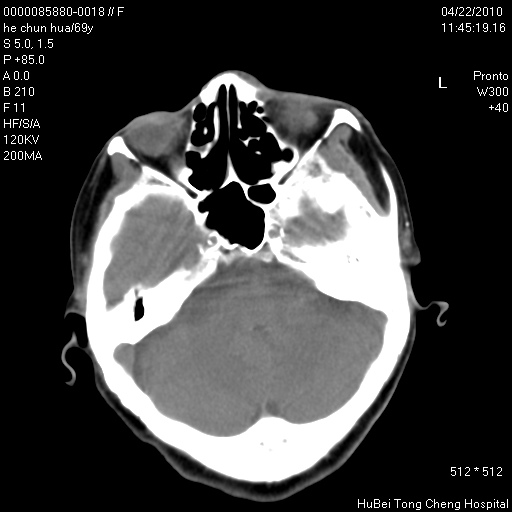

标题: CT25937:女,69Y

硬腭部包块十余年,渐进性增大。